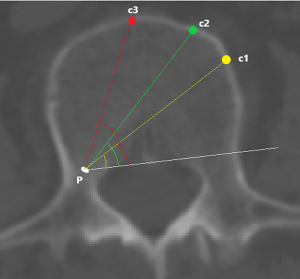

To investigate fully radiographic anatomy of PETOFPC, the authors chose to measure the distances from the posterior corner (P point, Figure 1) in lumbar spine to the corresponding targets.

Posterior corner in lumbar spine was selected as the screw entry point (P point) for oblique fixation. The screw entry point (P point) in posterior-inferior corner is the bony area between the upper margin of the pedicle and the upper endplate. The screw entry point (P point) in posterior-superior corner is the bony area between the lower margin of the pedicle and the lower endplate (Figure 2). The corresponding targets are A, B, C, D, E, and F, respectively (A: the middle point of the contralateral anterior-middle 1/3, B: the contralateral anterior-middle point, C: the middle point of the contralateral side, D: the upper point of contralateral anterior-middle 1/3, E: the contralateral anterior-upper point, F: the middle-upper point of the contralateral side) in the contralateral anterior region (Figure 3).

c1: the angle between the projection, which is generated from the posterior corner of the upper vertebral body to contralateral front-middle 1/3 on the endplate, and the tangent line to the posterior border of the vertebral body.

c2: the angle between the projection, which is generated from the posterior corner of the upper vertebral body to contralateral anterior corner on the endplate, and the tangent line to the posterior border of the vertebral body.

c3: the angle between the projection, which is generated from the posterior corner of the upper vertebral body to the midpoint of the anterior border on the endplate, and the tangent line to the posterior border of the vertebral body.